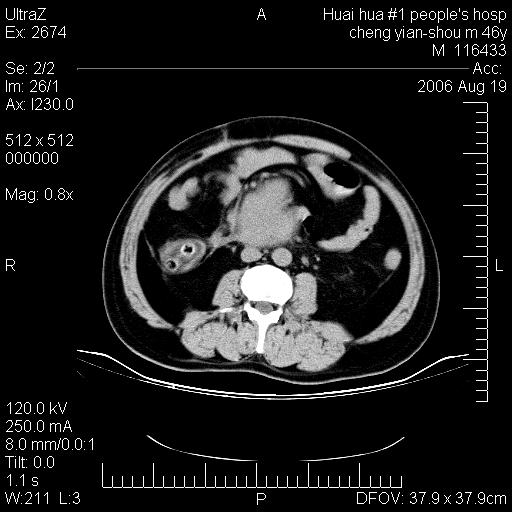

患者,男,46y。腹痛2月,消瘦。

十二指肠水平段占位,考虑间质瘤或平滑肌瘤。

肿块较大,腹膜后占位,境界欠清,周边脂肪密度较高呈条状影,有没有脂肪肉瘤可能,

缺少完整的三期图像。考虑肠系膜脂膜炎mp(肿块型)。

十二指肠水平段占位,考虑间质瘤。

首先考虑小肠间质瘤。

十二指肠水平段软组织密度占位,考虑间质瘤可能性大。

腹膜后占位,境界欠清,考虑来源于十二指肠病变,间质瘤或平滑肌肉瘤可能性大。建议活检。

手术病理结果:原发性小肠恶性淋巴瘤(primary gastrointestinal lymphoma,pgil)是原发于胃肠的淋巴网织系统的恶性肿瘤,在结外淋巴瘤中居第一位,该病少见,临床无特异性,诊断困难,术前主要依靠影像学诊断。胃肠道本身具有较丰富的淋巴组织,因而胃肠原发性淋巴瘤是结外淋巴瘤最常见的部位,文献报道约占胃肠道恶性肿瘤的1%~4%,其中胃约占50%~70%,小肠约占35%~70%,结肠约占4%~6%。影像检查在pgil的诊断及分期中有重要的作用,ct是很有价值的检查方法。

胃肠淋巴瘤病理特点:胃肠道原发性淋巴瘤起源于胃肠壁固有层和黏膜下层的淋巴组织即胃肠粘膜相关淋巴组织(malt),多为粘膜相关淋巴瘤。病理上通常为非霍奇金淋巴瘤,且决大多数来源于b淋巴细胞,很少见于霍奇金淋巴瘤。胃肠原发淋巴瘤比胃肠道癌的发病率要低的多,最常见于胃,其病因可能跟幽门螺杆菌感染有关。幽门螺杆菌能引起胃粘膜损害,引起炎性及免疫反应,淋巴细胞聚集并形成滤泡,可影响胃的正常生理功能,导致胃淋巴瘤的发生。单纯性小肠淋巴瘤是常见好发于回盲末端,受累的肠段较长,可单发、多发,甚至累及整个小肠。原发性大肠淋巴瘤罕见,以直肠和盲肠最多见。病变大体观可表现为胃肠腔内外的肿块,也可表现为从黏膜下到浆膜面肠壁的纵向浸润,并且常常伴有肠系膜淋巴结肿大。任何情况下,肿瘤几乎总是导致一定程度的肠壁增厚,可对称或不对称,病变与正常组织间常无明确分界,肠腔可狭窄、正常或动脉瘤样扩张,后者主要是肿瘤在肠壁内浸润,破坏肠壁内植物神经丛所致。以上改变成为ct检测病变的病理基础。

肠道淋巴瘤的ct表现分为4类

1) 壁内浸润型, (2)多发结节型, (3)肠系膜受累伴腔外肿块型(本型就是),(4)肿块型。